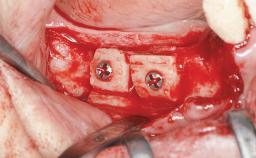

Staged bone augmentation of the alveolar ridge is indicated whenever a proposed implant site is deficient and will not support implant placement with simultaneous grafting. This is particularly true of healed sites presenting with facial flattening of the ridge. Since primary stability cannot possibly be achieved in this situation, it is recommended to use a staged approach with guided bone regeneration (GBR) for correct three-dimensional placement of the implant. In the anterior maxilla, staged GBR procedures are conducted not only to provide adequate bone volume for implant placement but also to restore a proper and stable contour of the orofacial ridge for improved long-term esthetics. A case is presented that demonstrates the technique for single-tooth replacement utilizing a staged approach with a particulate grafting material. A 50-year-old man whose tooth 11 was missing presented for consultation to the Center for Implant Dentistry in January 2010.

Bone Augmentation Horizontal|Staged

Augmentation Materials Allogenous|Membrane

Bone Volume Deficient horizontally, requiring prior grafting